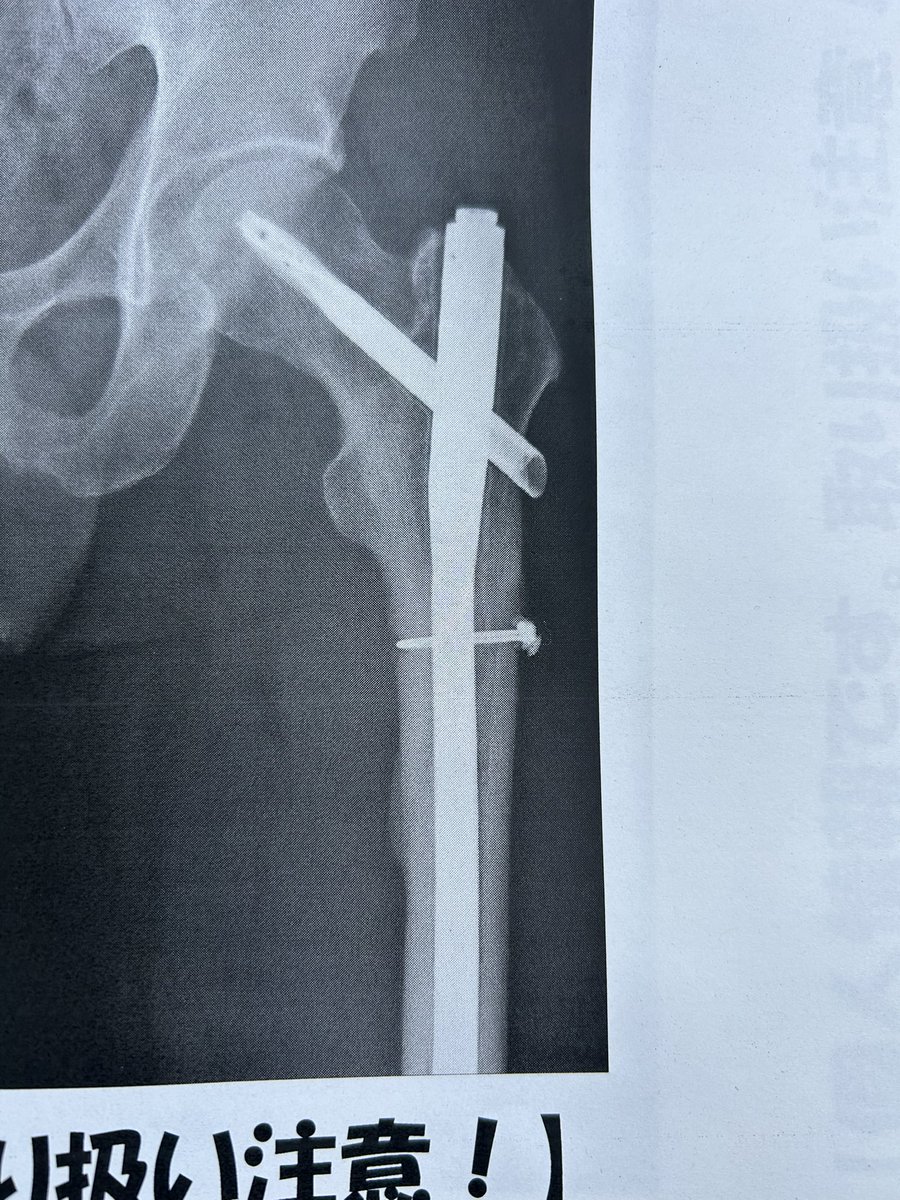

主に自転車&その他趣味(漫画&アニメ)アカ。デブは嫌なので3本ローラーで痩せようともがく引き篭もりのオッサン。650c難民。 2025/3/23落車し大腿骨骨折してリハビリ中〜